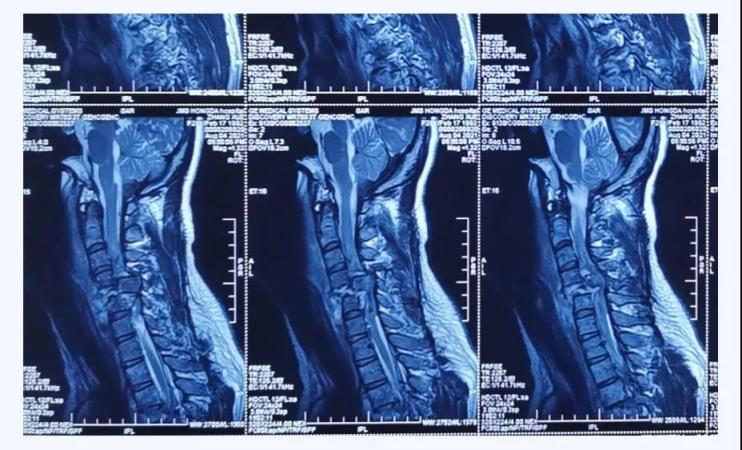

术前核磁

经查,病人确诊为“颈椎骨折脱位 、颈髓高位损伤四肢瘫”,以致四肢感觉运动均丧失。第五颈椎椎体完全脱位于后方椎管内,颈脊髓损伤严重,这类损伤导致脊髓水肿向上蔓延,可殃及呼吸循环控制中枢,患者随时都有呼吸循环骤停危及生命的风险。我院骨科首席专家、业务院长乔建民教授闻讯赶到医院进行紧急救治。一般的颈椎骨折脱位,只需将脱位的椎体复位并固定即可,但该患者由于脱位的第5颈椎椎体完全脱位至椎管内,导致相应节段颈脊髓受到严重挤压、损毁、变形,已无法手术将其复位,只能选择切除。手术部位是高位颈脊髓神经,并紧邻椎动脉,稍有不慎就会加重损伤,危及生命。手术难度之高、风险之大,是可想而知的。要完成这台如此高难度的手术,不单单是对术者技术能力的考验,更是对医者心智和意志的挑战。

时间就是生命!为给年轻的颈脊髓损伤患者夺得宝贵的黄金救治时限,具有多年颈椎骨折脱位手术成功经验的乔建民院长带领骨科团队当机立断、连夜组织讨论,迅速制定出最优手术方案。先进行“颈椎后路”手术,初步稳定脊柱序列,再进行“颈椎前路”手术切除脱位的第五颈椎椎体,充分减压。手术的难点是切除颈五椎椎体时非常困难,极易造成颈脊髓神经二次损伤,甚至加重病情危及生命。